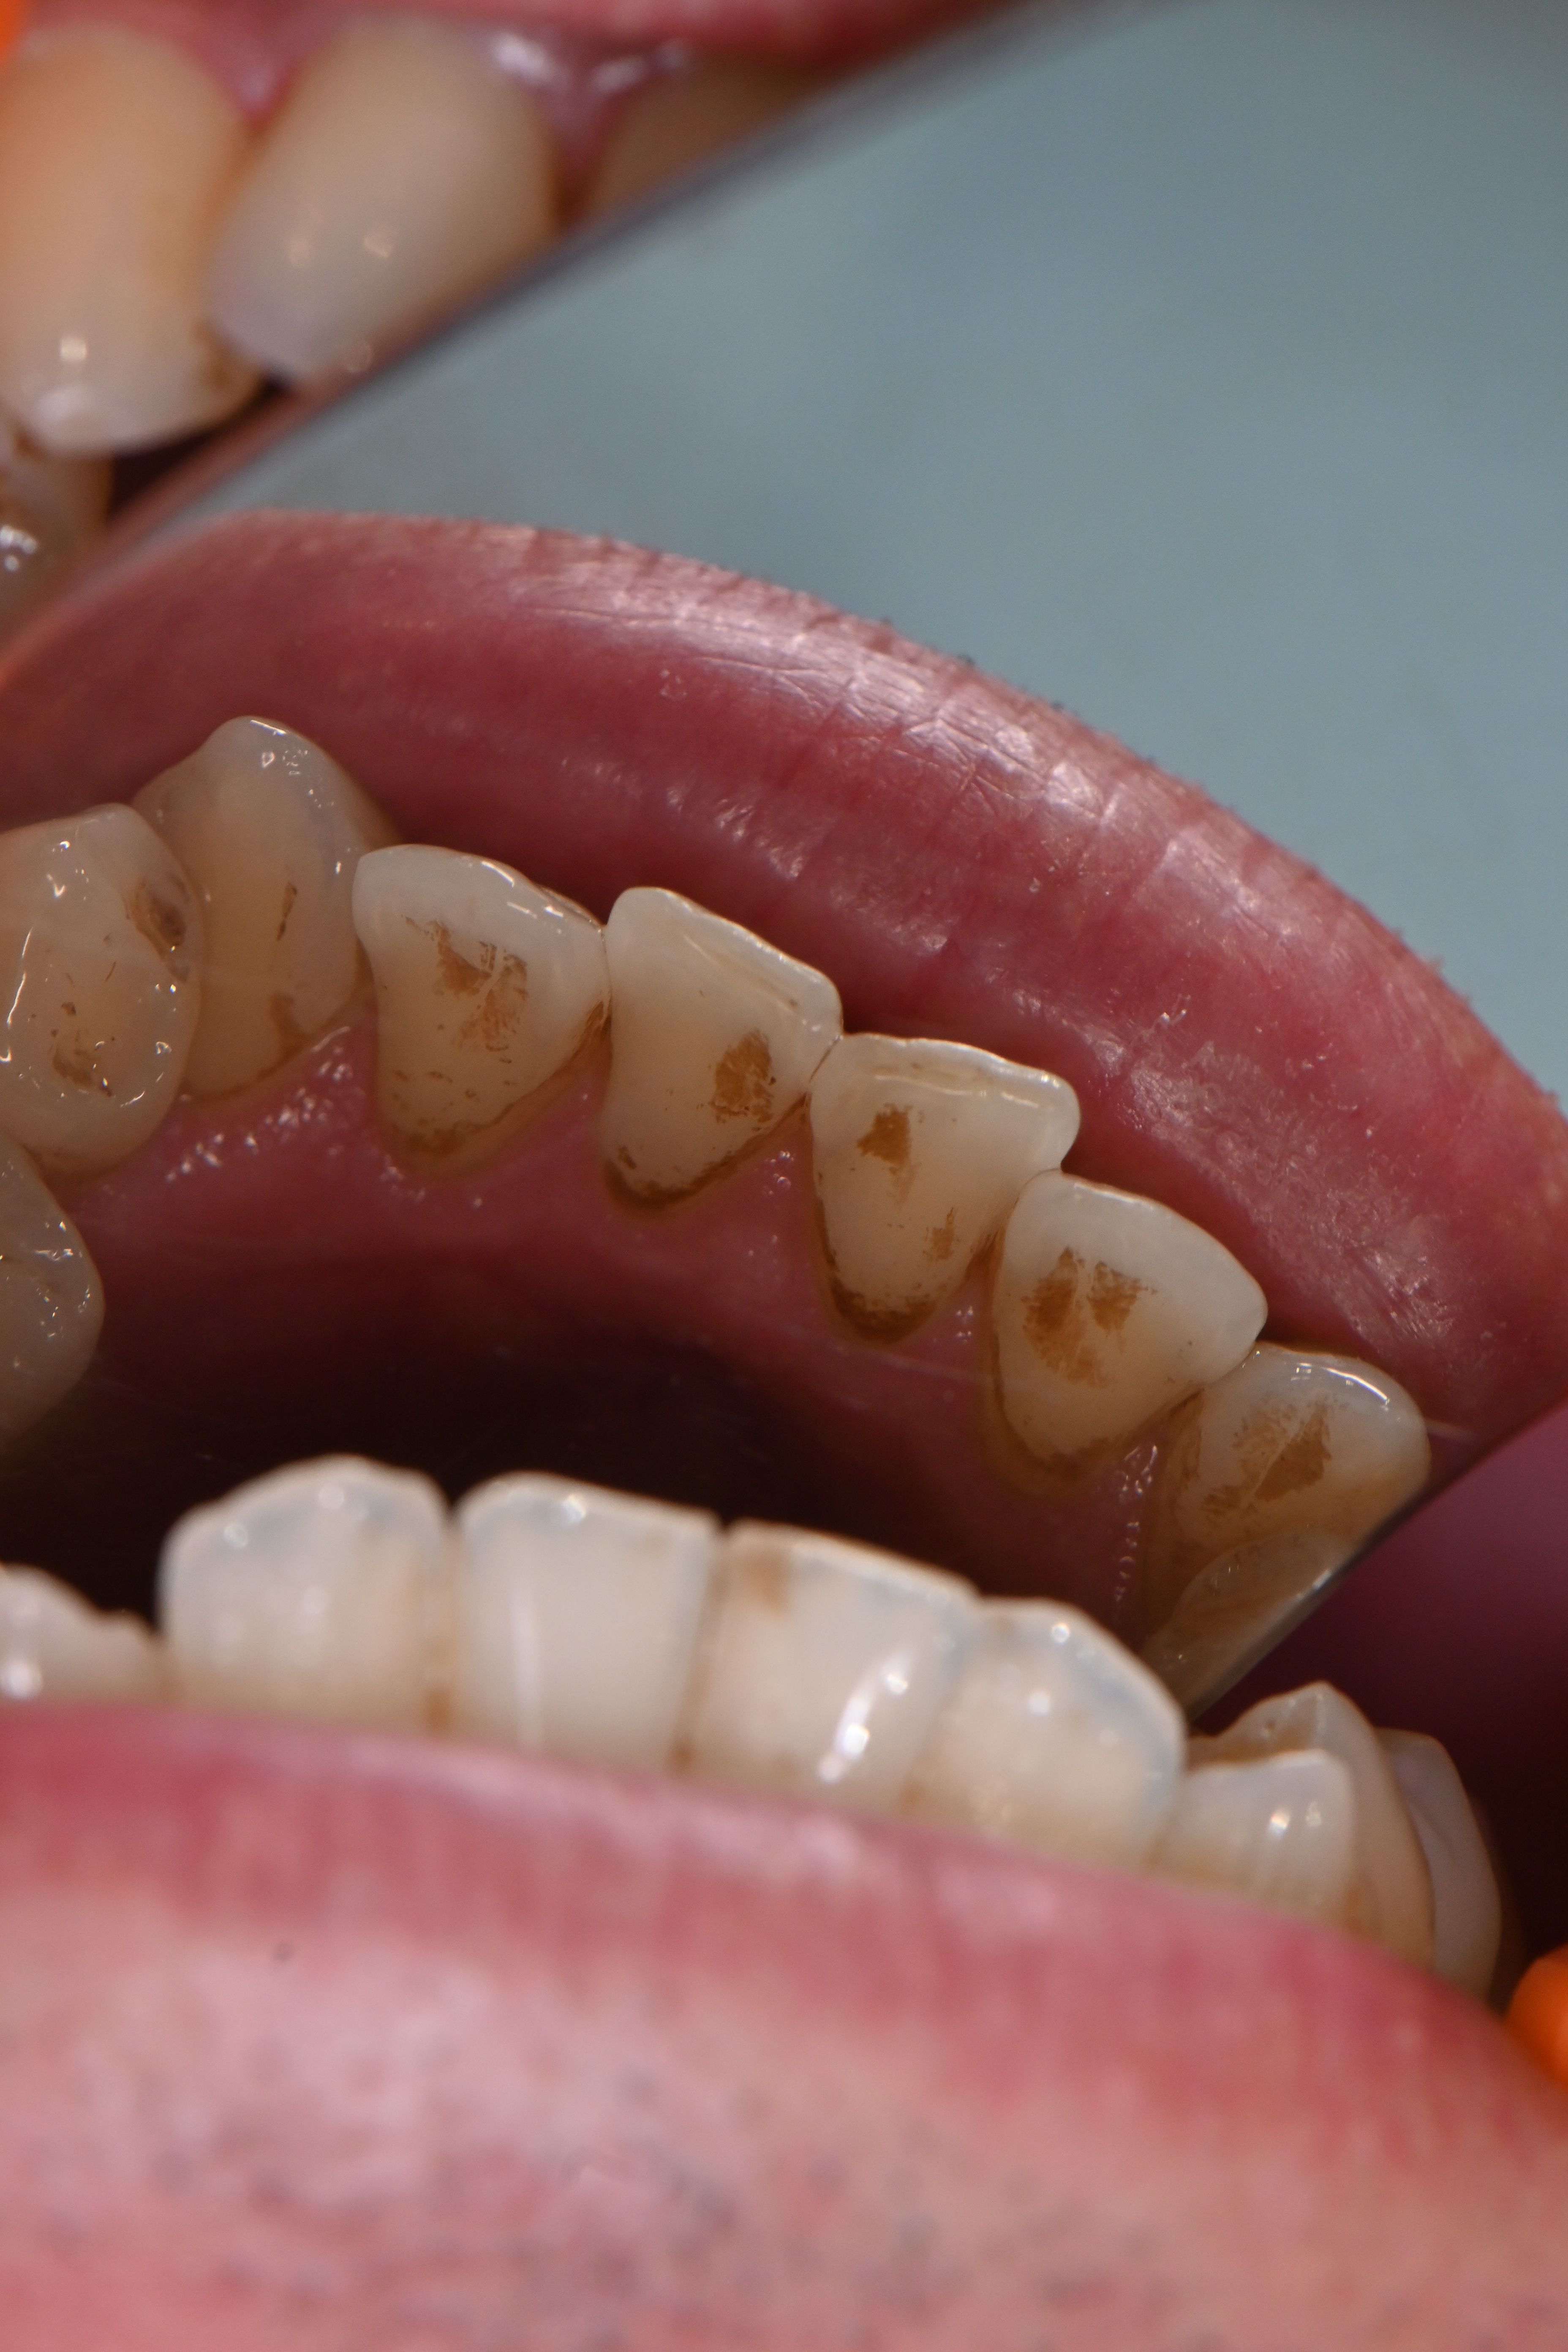

今回は全体的に着色が気になる方の症例です。

他の歯医者さんで以前からエアフローで着色を除去されてきた患者様ですが、前回してから半年期間が空いてしまったら再度着色が目立つようになったのこと💦

細かい着色をエアフローでしっかり除去して、仕上げにリナメル(歯の細かい傷を埋めてくれる)を塗布しました✨

場所によっては分厚い磨き残しがあり、そこに着色していた箇所もあったため歯磨き指導も一緒にさせていただきました。